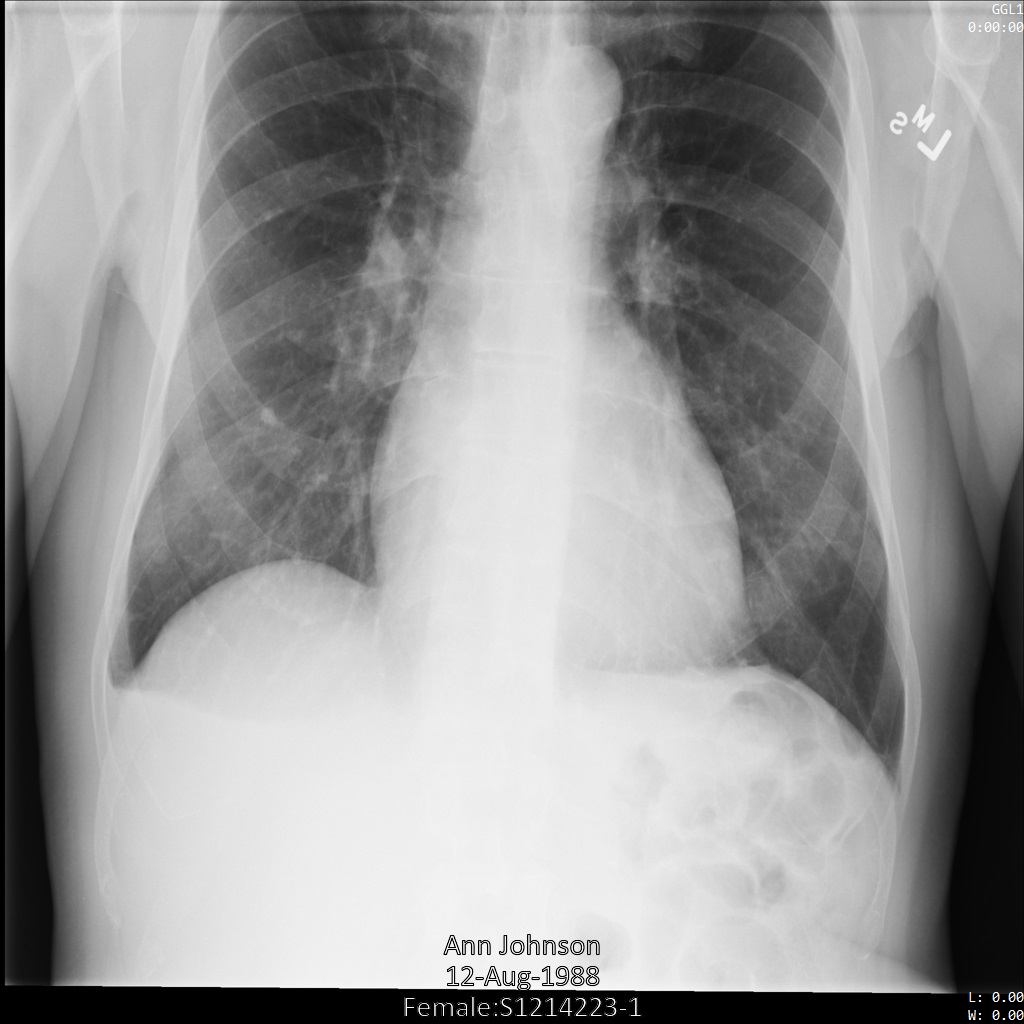

以下の各セクションでは、DICOM データを匿名化するさまざまな方法について、例を示しています。また、それぞれの例で匿名化された出力画像を示しています。各例では、入力として以下の元画像を使用しています。

各匿名化オペレーションからの出力イメージをこの元のイメージと比較して、オペレーションの効果を確認できます。

Cloud Healthcare API に画像を送信すると、画像は次のように表示されます。画像の上部隅に表示されているメタデータは削除されていますが、画像の下部にある焼き付き保護対象保健情報(PHI)は残ります。焼き付きテキストも削除するには、画像の焼き付きテキストを削除するをご覧ください。